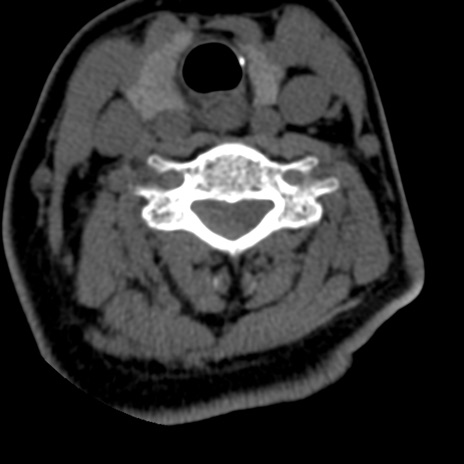

症例50 頚椎CT(横断像)

頚椎CT